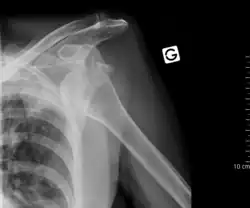

Luxación es la lesión en la cual los segmentos óseos que forman una articulación se separan. La luxación de hombro, o luxación escapulohumeral ocurre con frecuencia debido a la gran amplitud de movimientos que presenta esta articulación. Generalmente es una luxación anterior, es decir la cabeza del húmero se sale de su posición normal en la cavidad glenoidea de la escápula y se coloca delante, haciendo muy difícil y doloroso cualquier tipo de movimiento en el que deban desplazarse estos elementos óseos. Suele ocurrir por un traumatismo, siendo muy frecuente en la práctica deportiva. El tratamiento requiere la colocación mediante maniobras especiales del humero en su lugar correcto, no debe nunca intentar realizarse esta acción por personas que no sean profesionales sanitarios.[2]